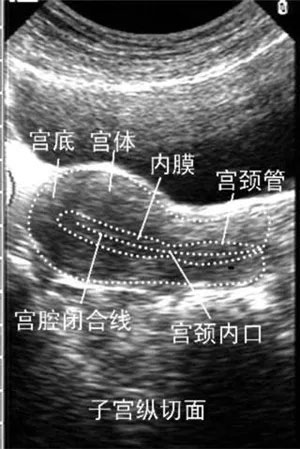

专家指出:导致试管婴儿治疗失败的原因有很多,其中子宫内膜好坏对于试管婴儿胚胎移植着床有直接的影响,所以,我们在做俄罗斯试管婴儿前一定要调养好自己的子宫内膜,多了解一些试管婴儿知识,这对于提高试管婴儿的成功率有很大的帮助。